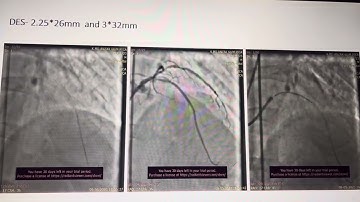

How to perform the reverse crush technique for bifurcation stenting